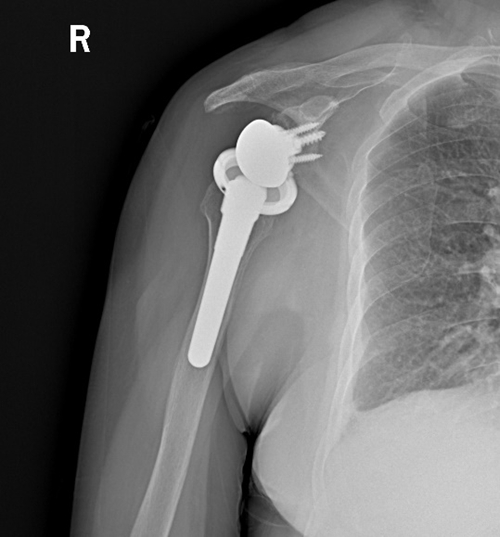

术前:肩袖巨大缺损,肱骨头磨损变形

术后:人工假体安装良好